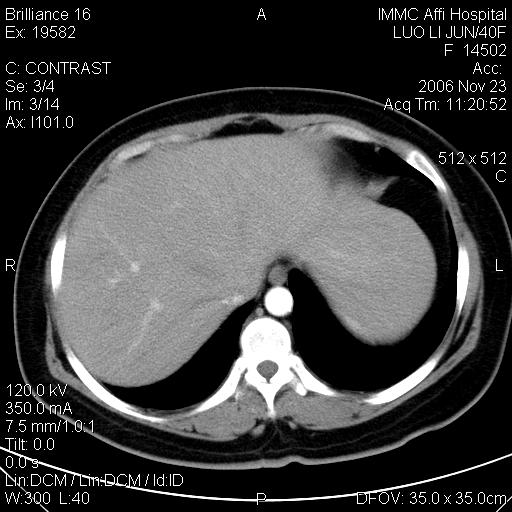

标题: CT5664:我也发一个肝脏的片子大家看看

很典型的肝癌。

典型肝癌

肝癌

速升速降,典型肝癌.

支持-----考虑肝癌----[-从片上看增强早期应该是动脉晚期即门脉早期]

是啊,典型的早出早归!

快进快出典型肝癌.

病灶好圆!可能恶性度不高。

不能除外肝细胞腺瘤吧,还是得结合病史。

很好的片子,可惜增强做的比较失败,a期时间没有把我好,实际到了静脉早期了,否则会更典型。

最终考虑是肝腺瘤